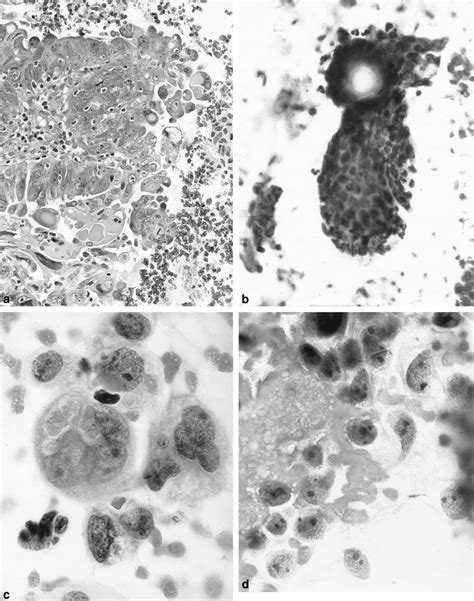

Receiving a diagnosis of Papillary Serous Carcinoma can be an overwhelming and life-altering experience. As a subtype of epithelial cancer that most commonly originates in the ovaries, fallopian tubes, or the peritoneum, it is characterized by its distinct cellular structure under a microscope, where the cells form small, finger-like projections known as papillae. Understanding the nature of this malignancy is the first step toward navigating treatment options, communicating with your medical team, and advocating for your own health journey. By breaking down the complexities of this condition, patients and caregivers can better grasp the diagnostic processes, treatment pathways, and the ongoing support structures available.

At its core, Papillary Serous Carcinoma is considered an aggressive form of cancer because it often presents at a later stage. Because the symptoms are frequently subtle—or even non-existent—in the early phases, the disease often spreads throughout the abdominal cavity before it is detected. The term "serous" refers to the fluid-producing cells from which the tumor arises, and "papillary" describes the architectural pattern of the cells.

• High-Grade Classification: Most cases are categorized as high-grade, meaning the cells look significantly different from normal cells.